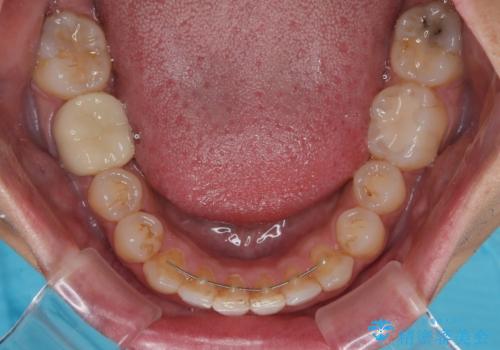

前歯のデコボコと突出感をマウスピース矯正できれいに

- 上下前歯のデコボコと突出感を気にして来院された患者様です。

目立たない装置を希望されたため、インビザラインによるマウスピース矯正を行うこととしました。

矯正治療後に銀歯をセラミックに替えたいとの要望があり、概ね歯列が整ったところで銀歯をセラミックに替え、仕上げにインビザライン1セットを使用して最終的に歯列を整えました。